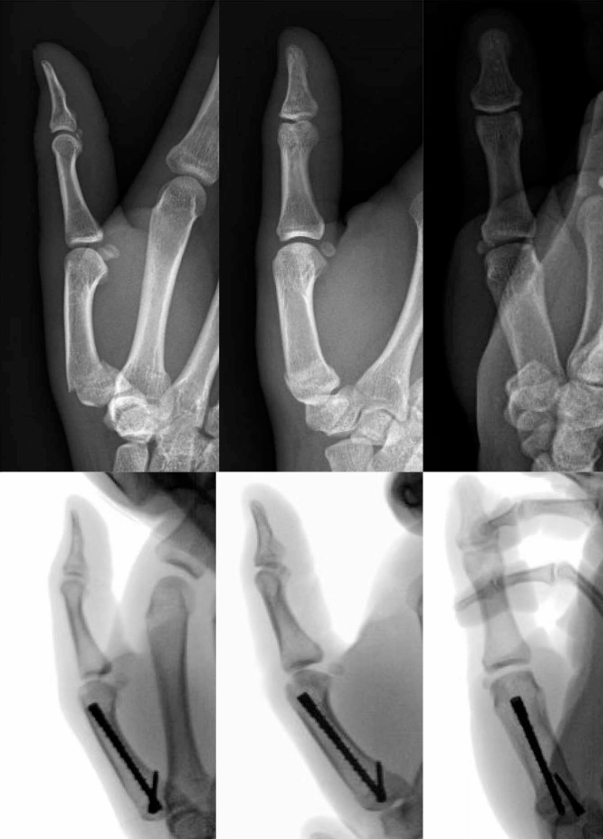

1. Percutaneous Screw Fixation for Metacarpal Head Fractures

微信图片_2026-04-27_153600_027.png

微信图片_2026-04-27_153538_627.png